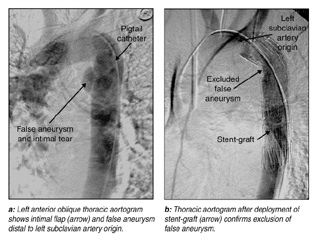

We felt that turning the patient to the lateral thoracotomy position for conventional surgical repair would risk further neurological deficit. Therefore, after discussing therapeutic options with the patient and his family, emergency endovascular stent-graft repair of the thoracic aortic injury was performed (see Box for technical details). CT angiography confirmed absence of extraluminal flow after the procedure. The patient subsequently underwent fixation of the lumbar spine injury using posterior rods, pedicle screws and bone graft. He made a complete neurological recovery. Three days after stent-graft insertion, he underwent video-assisted thoracoscopic evaluation of the left side of the chest for drainage of a large haemoserous pleural effusion. The thoracic aortic contour was normal, with minimal peri-aortic haematoma. Repeat CT angiography at six and 12 months confirmed thrombosis of the false aneurysm, with no complication related to the stent-graft repair, and the patient remains well 18 months after the injury.